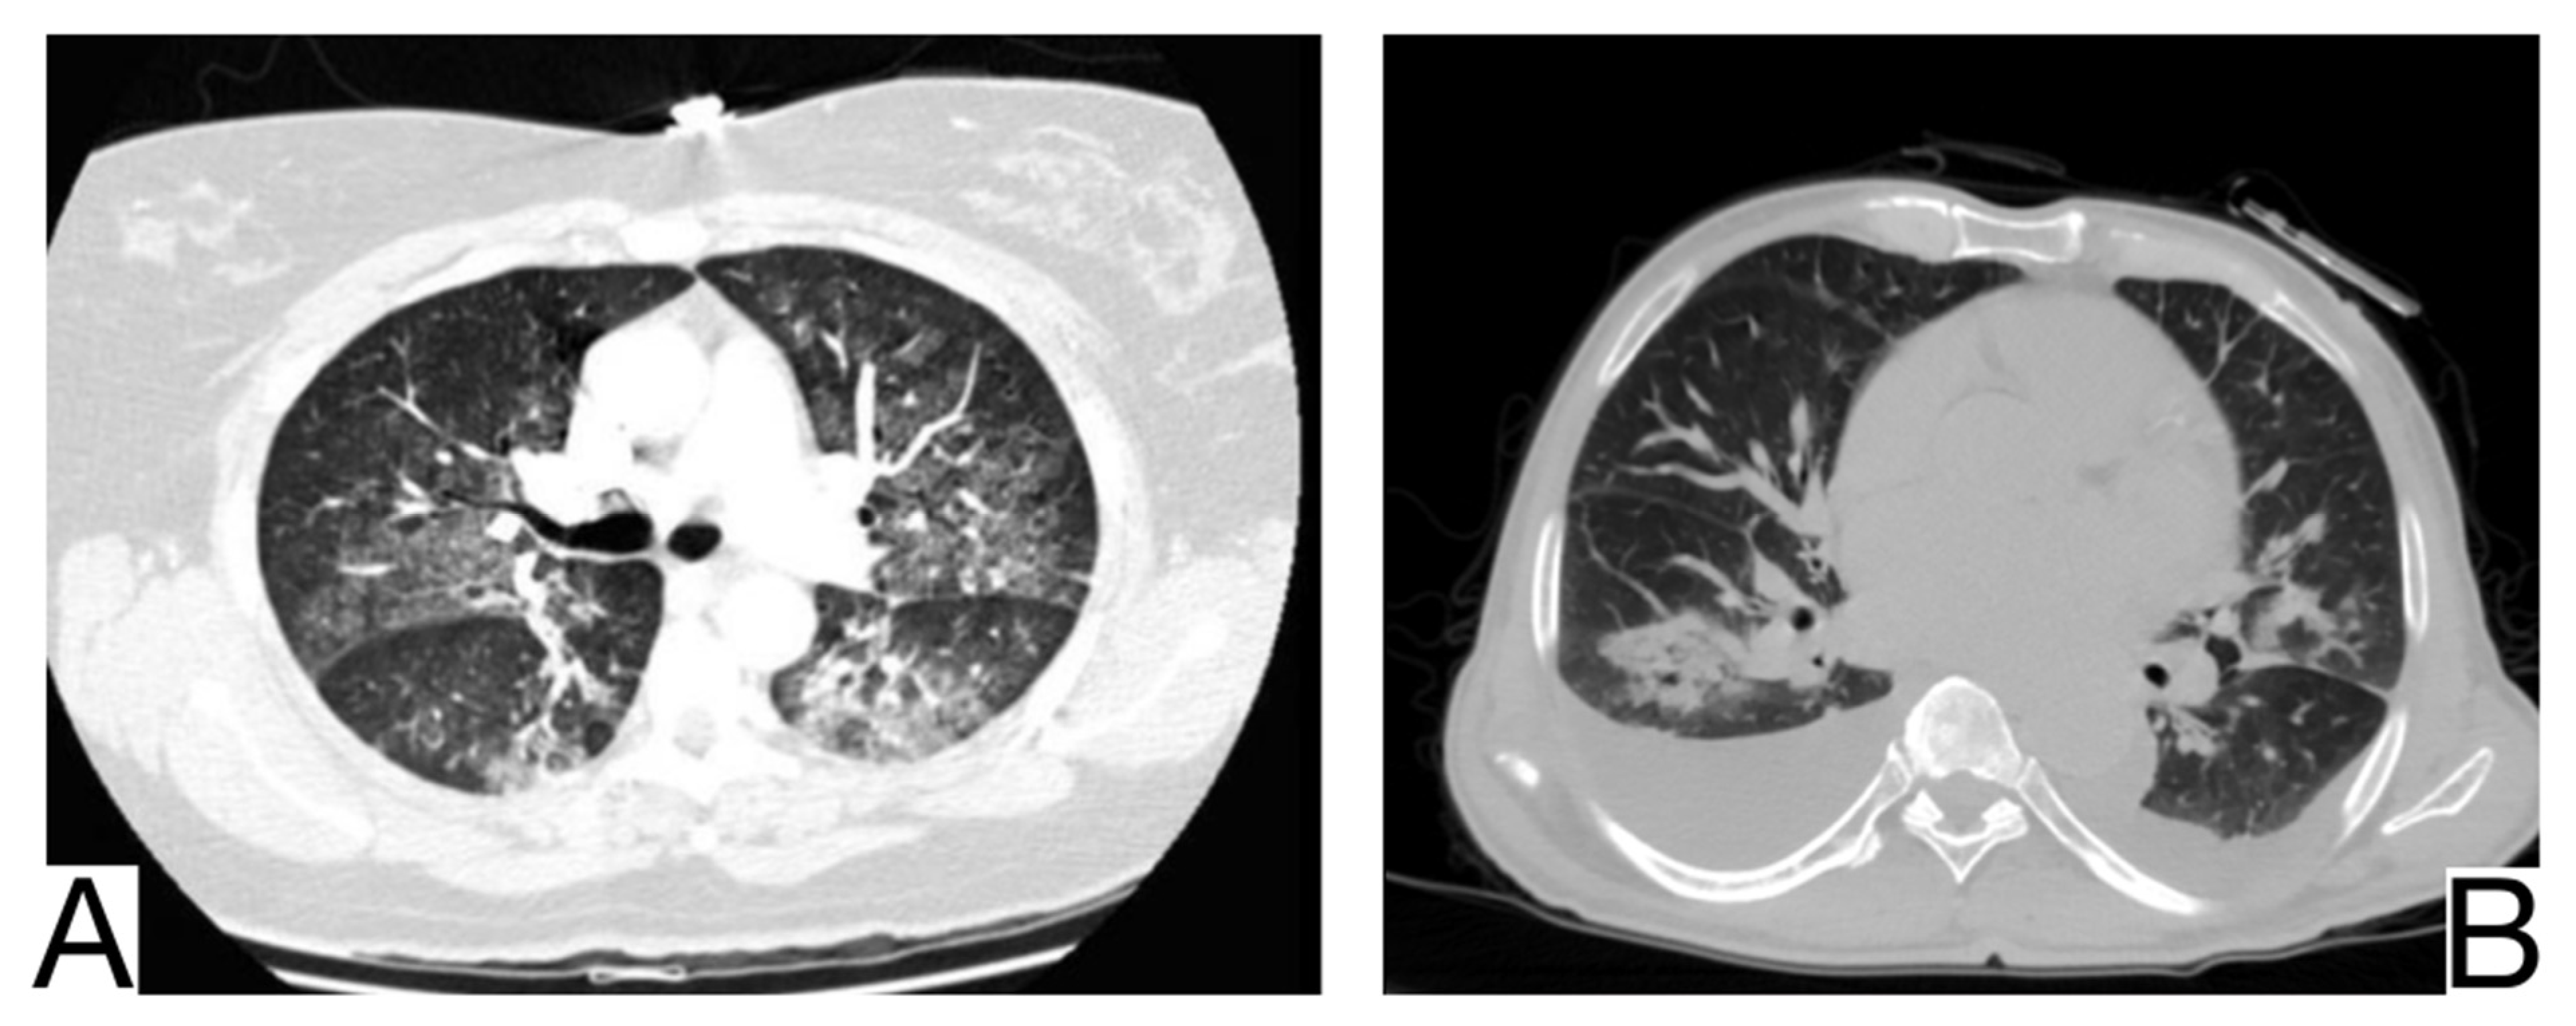

10.5.1. Acute Pulmonary Edema

10.5.2. Differential Diagnosis of COVID-19 Pneumonia with Acute Heart Failure